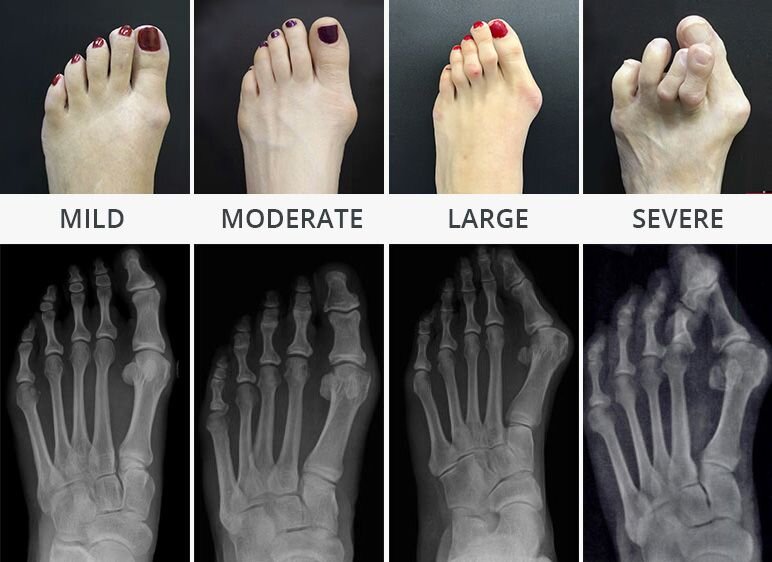

A hammer toes is a toe that curls or is buckled. This condition can be very painful and make fitting into shoes difficult. This deformity can cause skin lesions where infection introduction can occur mainly seen in diabetes or those with poor circulation. See a Manhattan hammer toe surgeon or foot doctor in New York sooner rather than later to treat this uncomfortable condition.

People ask NYC podiatrist every day to explain what caused their toe to become bent like this. This deformity occurs when the muscles that stabilize your toes lose the delicate balance among them and start to overpower each other. This causes your toe to bend or become stuck in a curled position. This can become painful because the contracted toes bump against the top of your shoe. The ball of the foot can also become painful since the toes are not carrying any weight as they contract off the ground. It’s possible for less invasive methods to help, but if your case is serious, your NYC podiatrist may recommend hammer toe surgery.